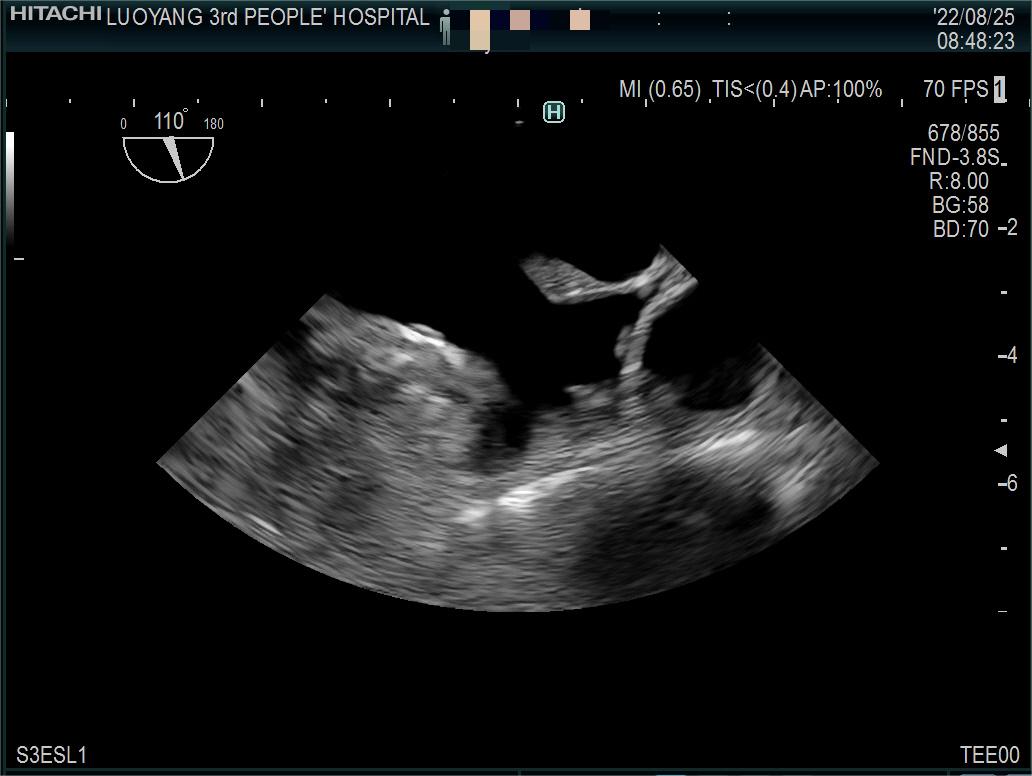

8月25日,经过我院超声科积极筹备,相关科室的大力配合下,我院首例经食道心脏超声检查顺利开展。

据了解,经食管超声心动图检查是将超声探头插入食管,直接贴在心脏的后方,从后向前观察心脏、血管和血流动力学情况,避免了气体及脂肪的干扰。由于食道超声的探头频率高于普通经胸超声探头,可以扩大心脏的扫描范围,提高图像质量及细微分辨率。与经胸超声心动图相比,经食管超声心动图具有距心脏近、软组织影响少,避免了胸骨和肺组织干扰,能充分显示左、右心房,房间隔,心耳,肺静脉和主动脉等优点,能更加准确地诊断心脏细小病变及疑难疾病。特别是能明确因卵圆孔未闭导致的偏头痛及矛盾性栓塞患者的病因、并能有效评估房颤患者是否有血栓形成的危险性,为后续治疗提供可依据。